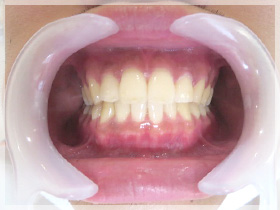

40代女性

ちゃんと噛めない、歯が弱いから治したい、歯が無いからなんとかしたい、歯を見せて笑いたい、顎が痛い

ちゃんとなんでも噛める様になったのと、審美的回復にも大変満足していただきました。

口元のハリも出て、唇がちゃんと出てきたと喜んでいただきました。

また顎の痛みもこの頃には無くなりました。良かったです。

1つ患者さんにお願いしたのは今迄コンプレックスにより口元を閉じる癖をやめていただき、歯を見せて笑顔を見せる練習をしてもらうようにしていただいたら素晴らしい笑顔になりました。